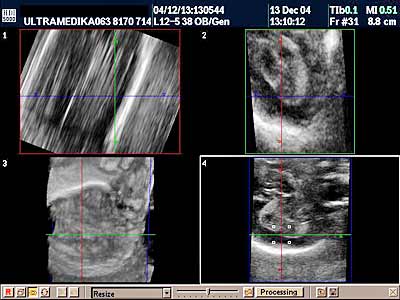

B) 3D Sono CT (trodimenzionalna) tehnika, dovodi do kvalitativnog pomaka u odnosu na prethodne godine. Naime 3D Sono CT (trodimenzionalna) tehnika nam omogućava dobijanje kompletnog volumenom mozga. Ako želimo da prikažemo u tri dimenzije krvne sudove koristimo 3D CPA tehniku. Ova tehnika je jako složena, zahteva dodatno vreme, izuzetno poznavanje anatomije i sonomorfološke ultrazvučne anatomije organa i organskih sistema, i sagledavanje promene u sve tri ravne, istovremeno. Da bi smo rendereisali - skupili sve informacije prosečno za to nam je potrebno oko 10 sekundi. Međutim, naknadnim multiplanarnim prikazivanjem i detaljnom analizom velikog broja dobijenih ultrazvučnih slika odgovarajućih preseka kompletne moždane cirkulacije potrebno nam je najmanje 10-15 minuta.